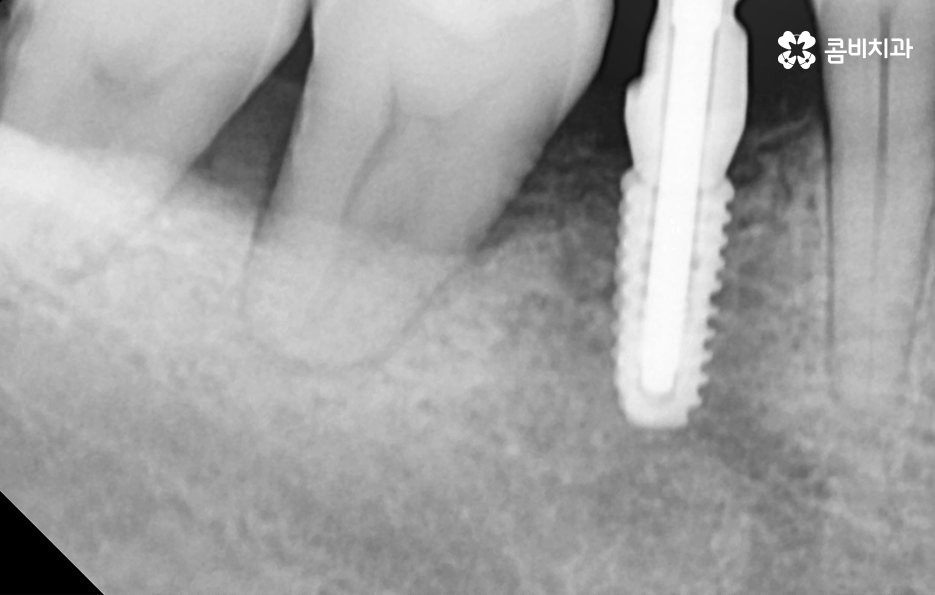

오늘 포스팅에서 소개드린 케이스의 경우 임플란트 치료 전에 치아교정을 통해 치료 계획을 세운 경우라면 이미 임플란트를 한 상태에서 교정에 대한 고민을 하는 분들도 있을 거예요

임플란트를 이미 한 상태에서 교정을 계획하는 경우에 대해 설명드리면 일반적으로 치열 위주로만 가지런하게 만들기 위한 치아교정은 임플란트가 크게 방해되지 않는 경우가 대부분이며 이미 치열이 삐뚠 상태에서 임플란트를 하셨던 경우에도 큰 문제가 아닌 경우가 더 많이 있는데요

임플란트를 제외한 자연치아를 우선적으로 치아교정을 하고 임플란트를 한 부위의 보철물은 새롭게 제작하거나 약간의 보철물 조정을 통해서 치료가 가능할 수 있어요